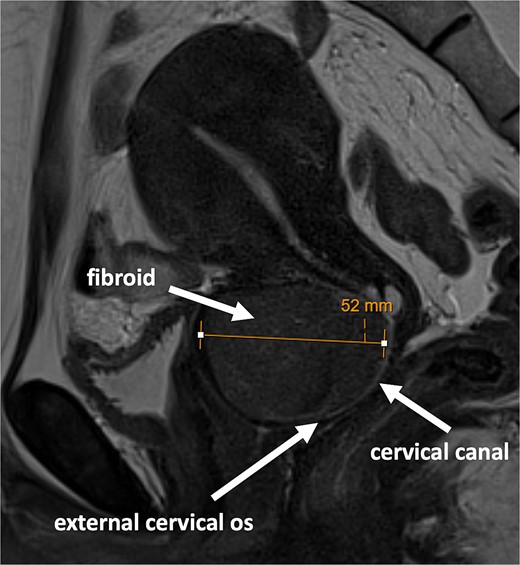

An outpatient magnetic resonance imaging (MRI) scan demonstrated a well-defined homogenous mass within the anterior cervix measuring 5.2 cm in maximum dimension (Fig. 1).

MRI scan showing large fibroid within the anterior cervical stroma with compression of the cervical canal.

The rest of the pelvic viscera appeared normal.